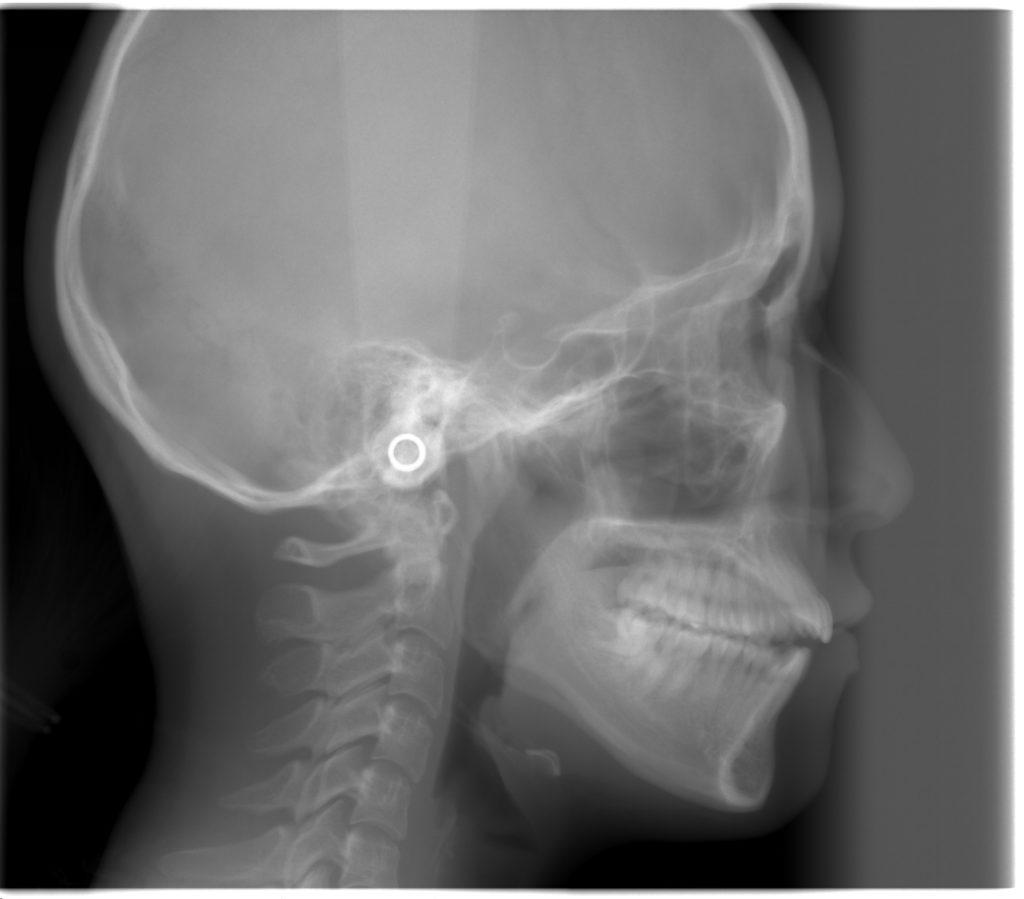

初診時の頭部X線規格写真

これは矯正治療で行う検査の中で、最も重要な検査の1つです。

頭蓋骨に対して、上顎骨、下顎骨の大きさや、上下の前歯の角度を測ります。

このレントゲンからは、上の前歯の角度が大きいこと、上下の前歯で咬めていないことが分かります。